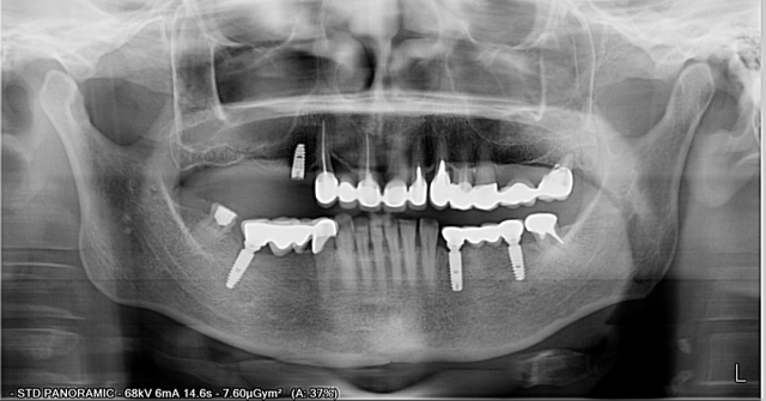

Dentalni implantati ugrađuju se u čeljust i njihovo učvršćivanje traje 3 do 4 mjeseca – kontrolira se rendgen slikom.

Kontrola rendgen slikom. Foto: Dental Centar Jelić

Postupak se izvodi u lokalnoj anesteziji i potpuno je bezbolan. Ukoliko je potrebo ugraditi više implantata, ugrađuju se istovremeno u jednoj posjeti. Nakon 3 do 4 mjeseca vrši se kontrola učvršćivanja i pristupa se izradi keramičkog mosta ili krunice.